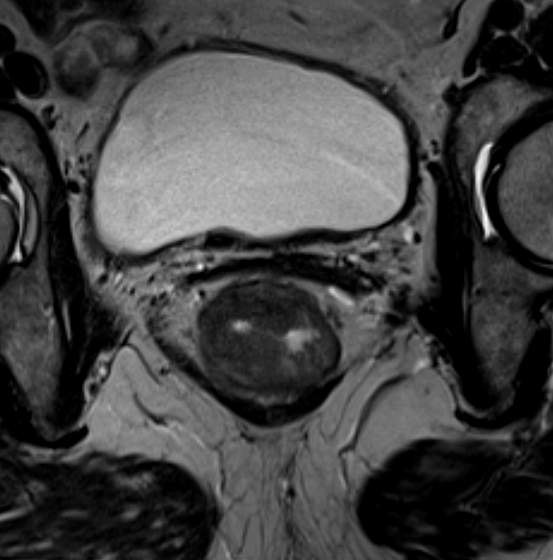

Магнитно-резонансная томография органов малого таза (прямой кишки)

Магнитно-резонансная томография не является методом выбора для первичной диагностики рака прямой кишки, но в ряде случаев является незаменимым помощником лечащему врачу. Оценка распространенности опухолевого процесса, выбор тактики лечения онкологического пациента, принятие решения о целесообразности и объеме оперативного вмешательства - те ситуации, когда МРТ НЕОБХОДИМА. Кроме того метод показан для контроля и оценки результатов лечения: хирургического, лучевого, химиотерапии; а также для определения дальнейшей тактики ведения пациента.

Возможности МРТ в диагностике рака прямой кишки:

• Визуализация опухоли, определение ее верхней и нижней границ, а также степени вовлечения в процесс кишечной стенки;

• Определение степени бокового распространения опухоли относительно стенки кишки, мезоректума и собственной фасции;

• Определение отношения опухоли к структурам тазового дна и сфинктерному аппарату;

• Определение состояния мышц тазового дна;

• Выявление и оценка состояния лимфатических узлов и лимфооттока в области малого таза;

• Контроль результатов хирургического лечения, лучевой терапии и химиотерапии; динамика.

Исходя из вышесказанного, на современном этапе развития медицины, МРТ прямой кишки является "ЗОЛОТЫМ СТАНДАРТОМ" при обследовании и дальнейшем ведении пациентов с диагнозом опухолевого поражения прямой кишки.